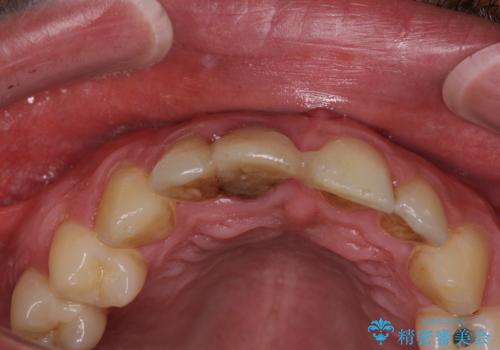

首の皮一枚で繋がっている前歯 1DAYインプラントでスムーズに治療

- 外れるたびに接着剤で応急処置を施してきた前歯のインプラント治療を希望して来院された患者様です。

磨き残しなどによるプラークの付着が多いため、仮歯の用意と手術アポイントの調整を行っている間に口腔内のクリーニングなどを施し、環境がある程度改善されたのちに、抜歯即時インプラント埋入、即時荷重(インプラント埋入時に仮歯の装着)の予定で治療を行うこととしました。

度重なる脱離により、表側の炎症が非常に強くなっており、歯を支える骨が失われている状態でした。

そのため、現在の位置よりも歯と歯肉の位置が退縮する方向に移動する可能性があり、前歯2本の歯肉位置が大きくずれることとなるため、本人との相談のうえ、天然歯が萌えているような歯肉状態とはならないものの、2本の段差が少ない状態にて治療を終えることとなりました。